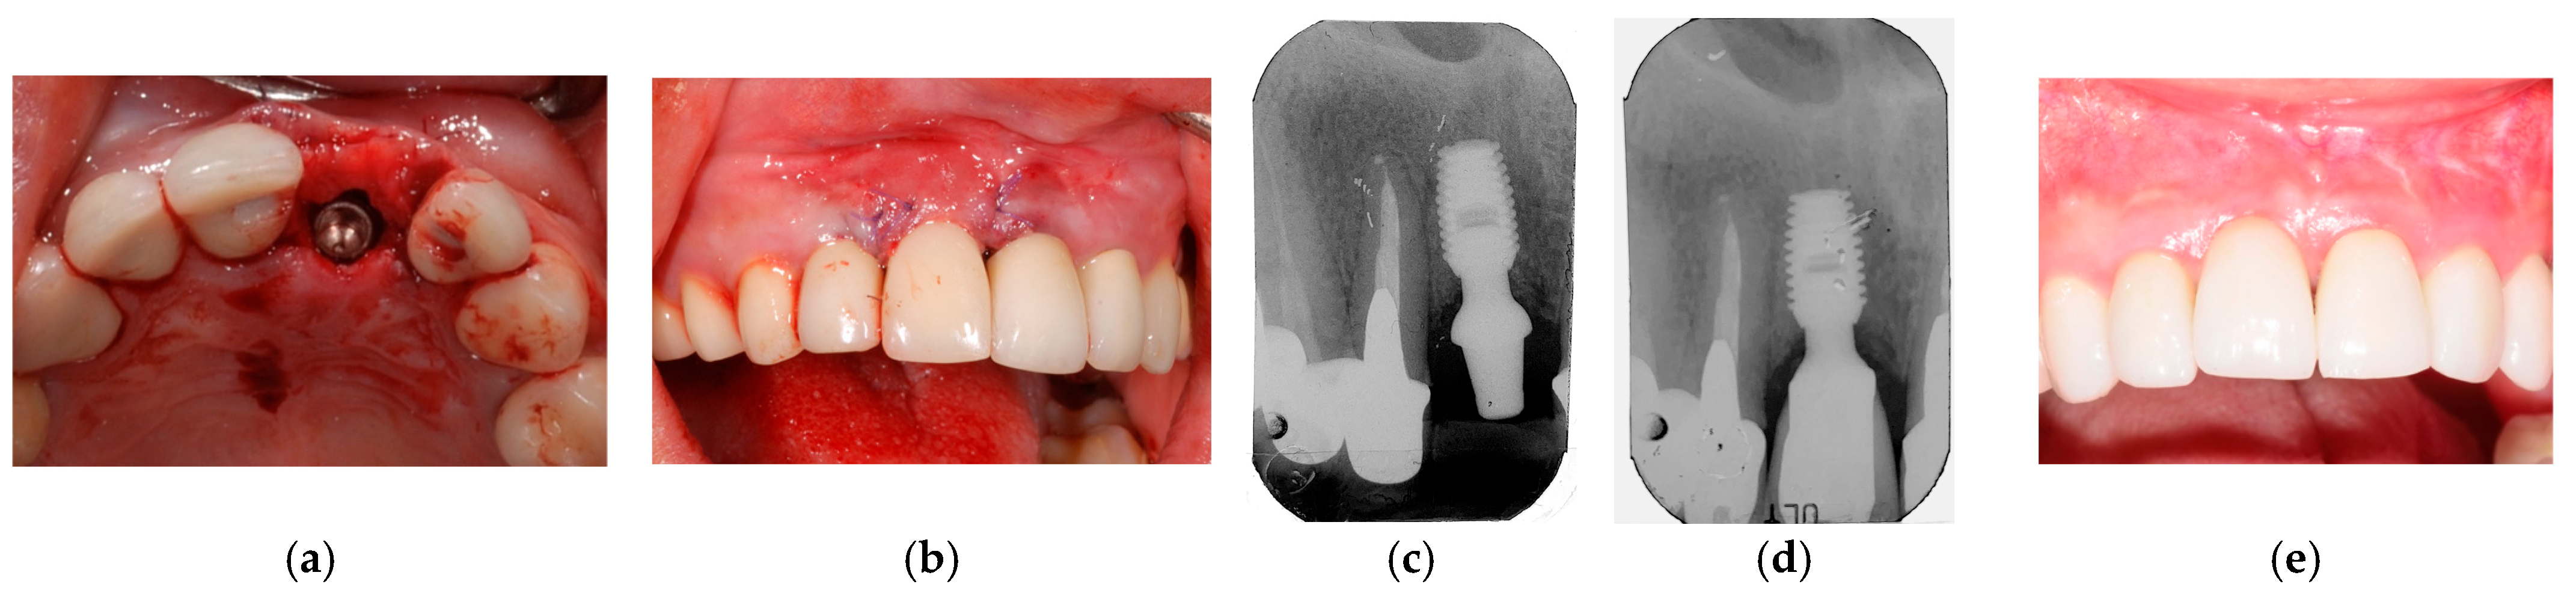

2.9. Clinical Cases and Study Diagram